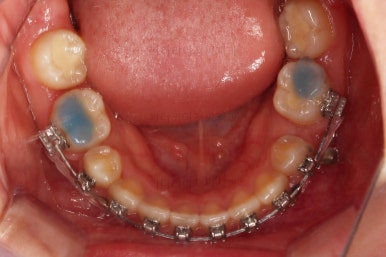

딱 한 개의 치아만 발치되어 있었는데 추가적으로 균형을 맞추기 위해 반대편 치아도 발치를 하고 아랫니 유치도 뽑았어요.

유치 어금니는 크기가 매우 크기 때문에 빈자리 만큼 모두 앞니를 뒤로 당기면 입이 너무 들어가게 된답니다.

따라서 얼마나 효과적인 방법으로 적절한 양만큼 어금니를 앞으로 당겨올 것인가가 이번 치료의 핵심이었어요.

입이 너무 들어가지 않게 중간중간 얼굴모습을 수시로 확인해 주고요.

미니스크류가 등장했네요.

아랫니는 아무 생각 없이 당기기 해주면 앞니가 너무 들어가 입이 합죽해질 수 있으니 앞니가 들어가는 양을 조절하기 위해서 미니스크류를 사용해주어요.

적절한 시기부터는 어금니만 100% 앞으로 당겨와야 했기 때문이죠.